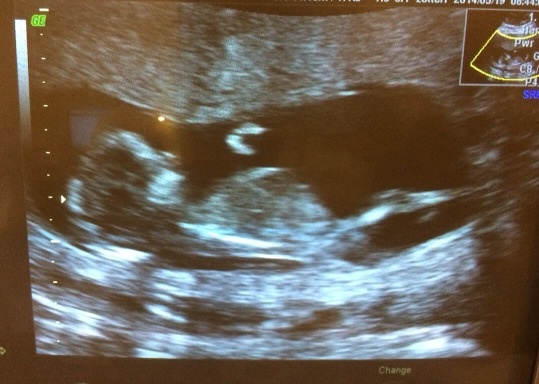

Imorgon har jag RUL och äntligen har det lilla börjat ge sig till känna i magen, igår kväll kände tom mannen utanpå magen. Så nu tvekar jag iaf inte på att något lever där inne, hoppas bara den är frisk också!Irmeline skrev 2014-05-11 21:47:09 följande:

Själv är jag i v. 20 och har RUL på tisdag. Nervös men hoppas allt är bra.

Priolistan ser ut såhär:

1. Bebis är frisk

2. Moderkakan har flyttat sig från öppningen

3. Vi får en fin bild

4. Vi får veta kön

Hoppas allt infrias, men viktigast är såklart nr 1.